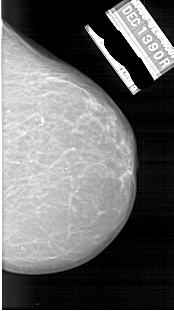

A_1866_1.RIGHT_CC

RIGHT_CC LINES 5581 PIXELS_PER_LINE 3121 BITS_PER_PIXEL 12 RESOLUTION 43.5 NON_OVERLAY